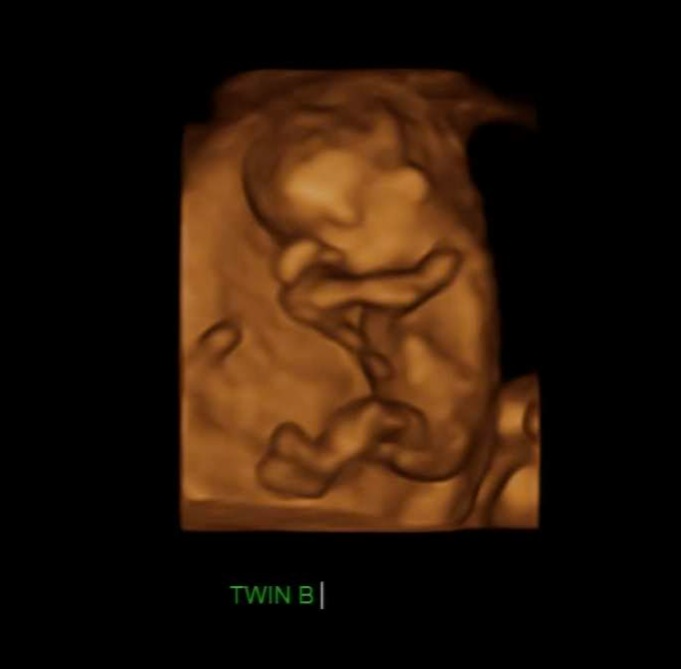

임신 16 ~ 20주가 되면 산모는 처음으로 태동을 느끼는데 이는 태아가 존재함을 표시하는 것이다. 이때 부모들은 태아의 움직임을 느끼면서 아이를 상상해 보게 된다.

저도 쌍둥이들이 뱃속에 있을 때 두 아이의 태동 차이가 컸습니다. 한 녀석은 정말 활발히 움직였고 한 녀석은 거의 움직이지 않았는데요.

한 번은 어쩌다가 의도치 않게 앞으로 넘어지게 됐는데 순간적으로 손으로 배를 가리긴 했지만 배 부분으로 정확히 떨어졌습니다. 그러고 나서 태동이 느껴지지 않는 겁니다 너무 걱정을 했고 바로 병원을 가야 하나 고민을 했는데요. 만약에 그 상황에서 안 좋았다면 양수가 터지거나 배에 통증이 오거나 다른 이상이 생겼을 텐데 딱히 그렇지는 않았습니다. 그렇게 한 10분쯤 지났을 때 갑자기 뱃속에서 꿀렁하는 겁니다. ㅎㅎㅎ 우와 그때의 쫀쫀한 마음은 정말 잊을 수가 없습니다. 움직여 주는 고마운지요. 그런데 한 녀석은 잘 움직이지 않는 것처럼 느껴지는 거예요. 그렇게 5분이 더 지난 후에야 한 녀석이 또 움직였습니다.